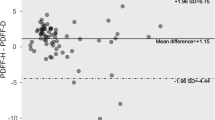

The mean HFF was 5.32 ± 6.83 % by 1H MRS and 9.49 ± 7.03 % by mDixon, when measured from areas matching locations for 1H MRS. Values of HFF assessed with mDixon correlated with those from 1H MRS (r = 0.972, p < 0.0001; Fig. 2a). Lower and upper limits of agreement in the corresponding Bland–Altman analysis (Fig. 2b) were 4.17 ± 3.22 %. The mean HFF value by mDixon was significantly higher (p < 0.001) than by 1H MRS. Differences between both methods did not depend on their mean value (slope = 0.03, p = 0.566).

Correlations and agreements between HFF by mDixon and 1H MRS (a–b). a Correlation between HFF by mDIXON and 1H MRS. HFF by mDIXON was obtained in the ROIs closely matching the VOIs in MRS (correlation coefficient: r = 0.972, p < 0.0001). b Bland–Altman plot for the two measurements. Lower and upper limits of agreement in the corresponding Bland–Altman analysis are 4.17 ± 3.22 %. Correlations and agreements between PFF by mDixon and 1H MRS (c–e). c The correlations of PFF by mDixon and 1H MRS. Analysis A (ROIs placed to closely match the VOIs of MRS) showed better correlation with PFF by 1H MRS (r = 0.804, p < 0.0001) than the ones from Analysis B (smaller ROIs avoiding the border of pancreas) (r = 0.574, p = 0.003). d The Bland–Altman plot of PFF by mDixon (Analysis A) and 1H MRS. Lower and upper limits of agreement for Analysis A are 5.56 ± 7.02 %. e The Bland–Altman plot of PFF from mDixon (Analysis B) and 1H MRS. Lower and upper limits of agreement for Analysis B are 2.65 ± 9.46 %, but in both analyses, the mean PFF values by mDixon are significantly higher (Analysis A: p < 0.001, Analysis B: p = 0.013) than by 1H MRS

Comparison of pancreatic fat fraction (PFF) using 1H MRS and mDixon

The mean PFF from the body of pancreas was 5.45 ± 5.86 % by 1H MRS and 11.01 ± 5.53 % by mDixon using Analysis A and 8.10 ± 2.85 % using Analysis B (Table 1). Since 1H MRS was obtained from the body region of pancreas, fat values of the body region by mDixon and those by MRS were correlated as shown in Fig. 2c (Analysis A: r = 0.804, p < 0.0001; Analysis B: r = 0.575, p = 0.003; Fig. 2c). Lower and upper limits of agreement in the corresponding Bland–Altman plot for Analysis A (Fig. 2d) and B (Fig. 2e) were 5.56 ± 7.02 and 2.65 ± 9.46 %, respectively. In both analyses, the mean PFF value by mDixon was significantly higher (Analysis A: p < 0.001, Analysis B: p = 0.013) than by 1H MRS. Differences between both methods did not depend on their mean value (slope = −0.06, p = 0.654) in Analysis A, but they did in Analysis B (slope = −0.851, p = 0.0002). The Bland–Altman plot in Analysis B suggests that PFF values by mDixon tend to larger/smaller values than those by 1H MRS, if the mean PFF value is smaller/larger at around 9 %.